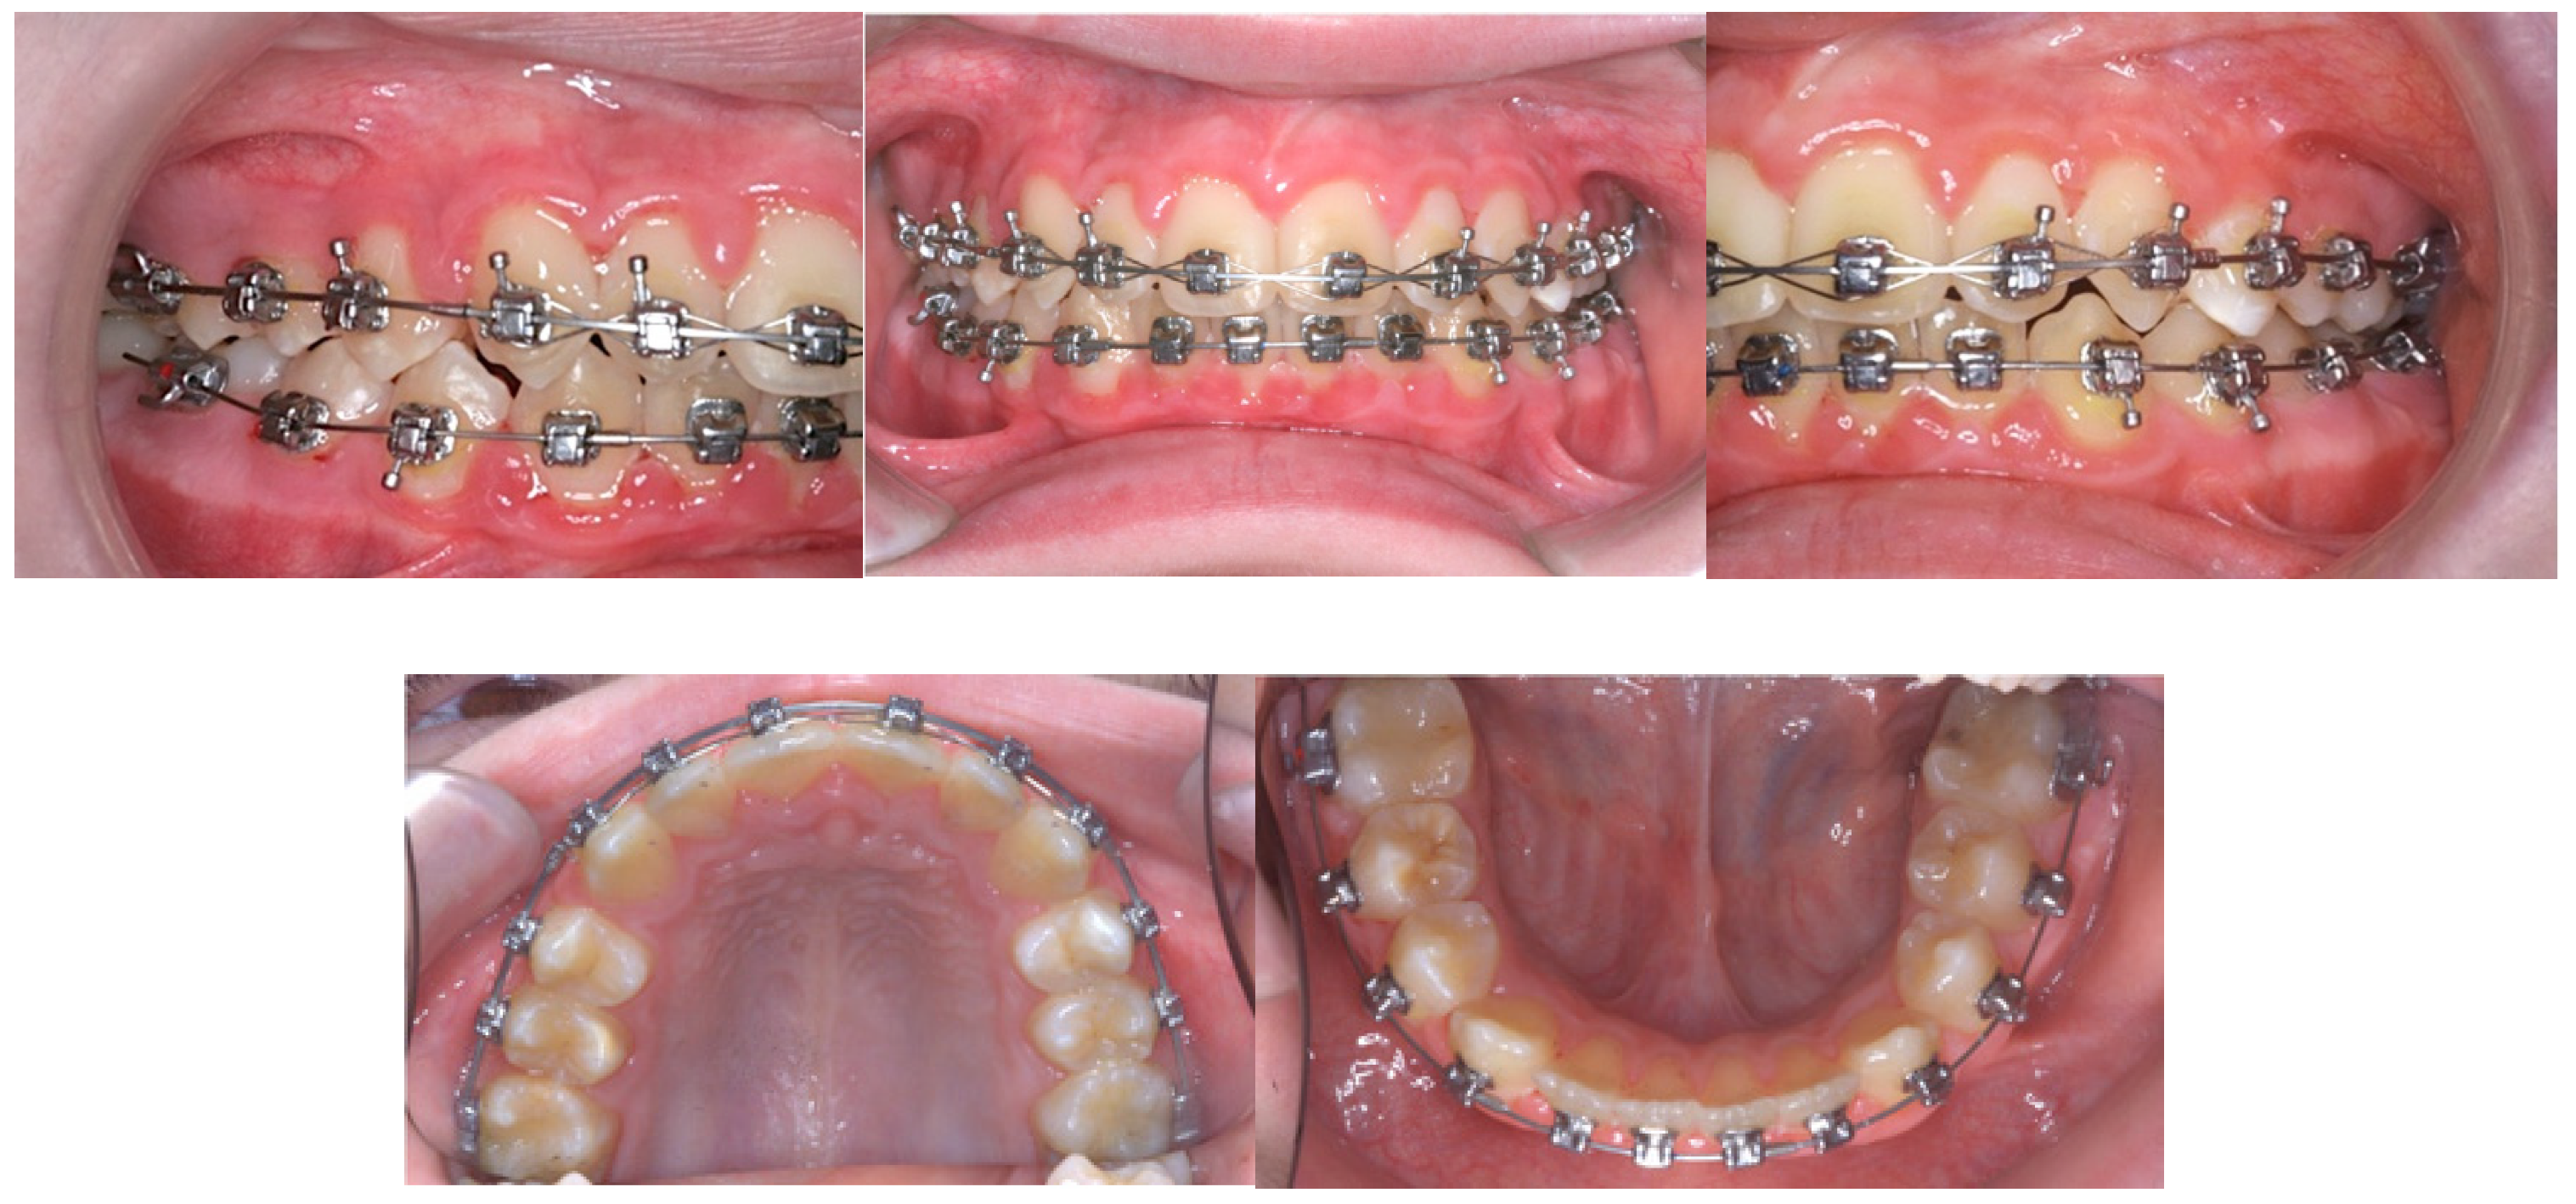

Figure 3.

Progress intra-oral photographs.

Initially, a 0.014-inch copper nickel–titanium (CuNiTi) archwire was used in the upper arch, and a 0.018-inch CuNiTi archwire was used in the lower arch to level and align the teeth. When the lower arch was bonded, bracket interferences required the placement of two bite turbos made from glass ionomer cement on the lower first molars. The maxillary archwire was changed to a 0.018-inch CuNiTi, and two composite bite turbos were applied to the palatal surfaces of the maxillary central incisors at month three. Early light short elastics (3/16″, 2 oz) were used from the upper first premolars to the lower first molars to protract the mandible and extrude the lower molars. Posterior bite turbos were removed as soon as the lower arch was aligned, at month five. At 11 months, upper and lower 0.014 X 0.025-inch CuNiTi archwires (Ormco, Glendora, CA, USA) were placed, followed by a 0.016 X 0.025-inch CuNiTi archwire. The light short elastics were replaced with conventional Class II elastics (¼″, 3.5 oz) from the upper canines to the lower first molars. A 0.018 X 0.025-inch CuNiTi archwire was subsequently used at month thirteen, and the upper anterior teeth were consolidated with a figure of eight steel ligature tie. The 0.019 X 0.025-inch stainless steel (SS) archwires were placed as the working archwires in both the upper and lower arches fifteen months after starting treatment. Fixed upper and lower lingual bonded retainers were placed at the end of active treatment, as the patient was approaching his fifteenth birthday.